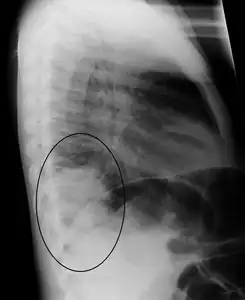

Normal lateral CXR

Right lower lobe pneumonia as seen on a lateral CXR